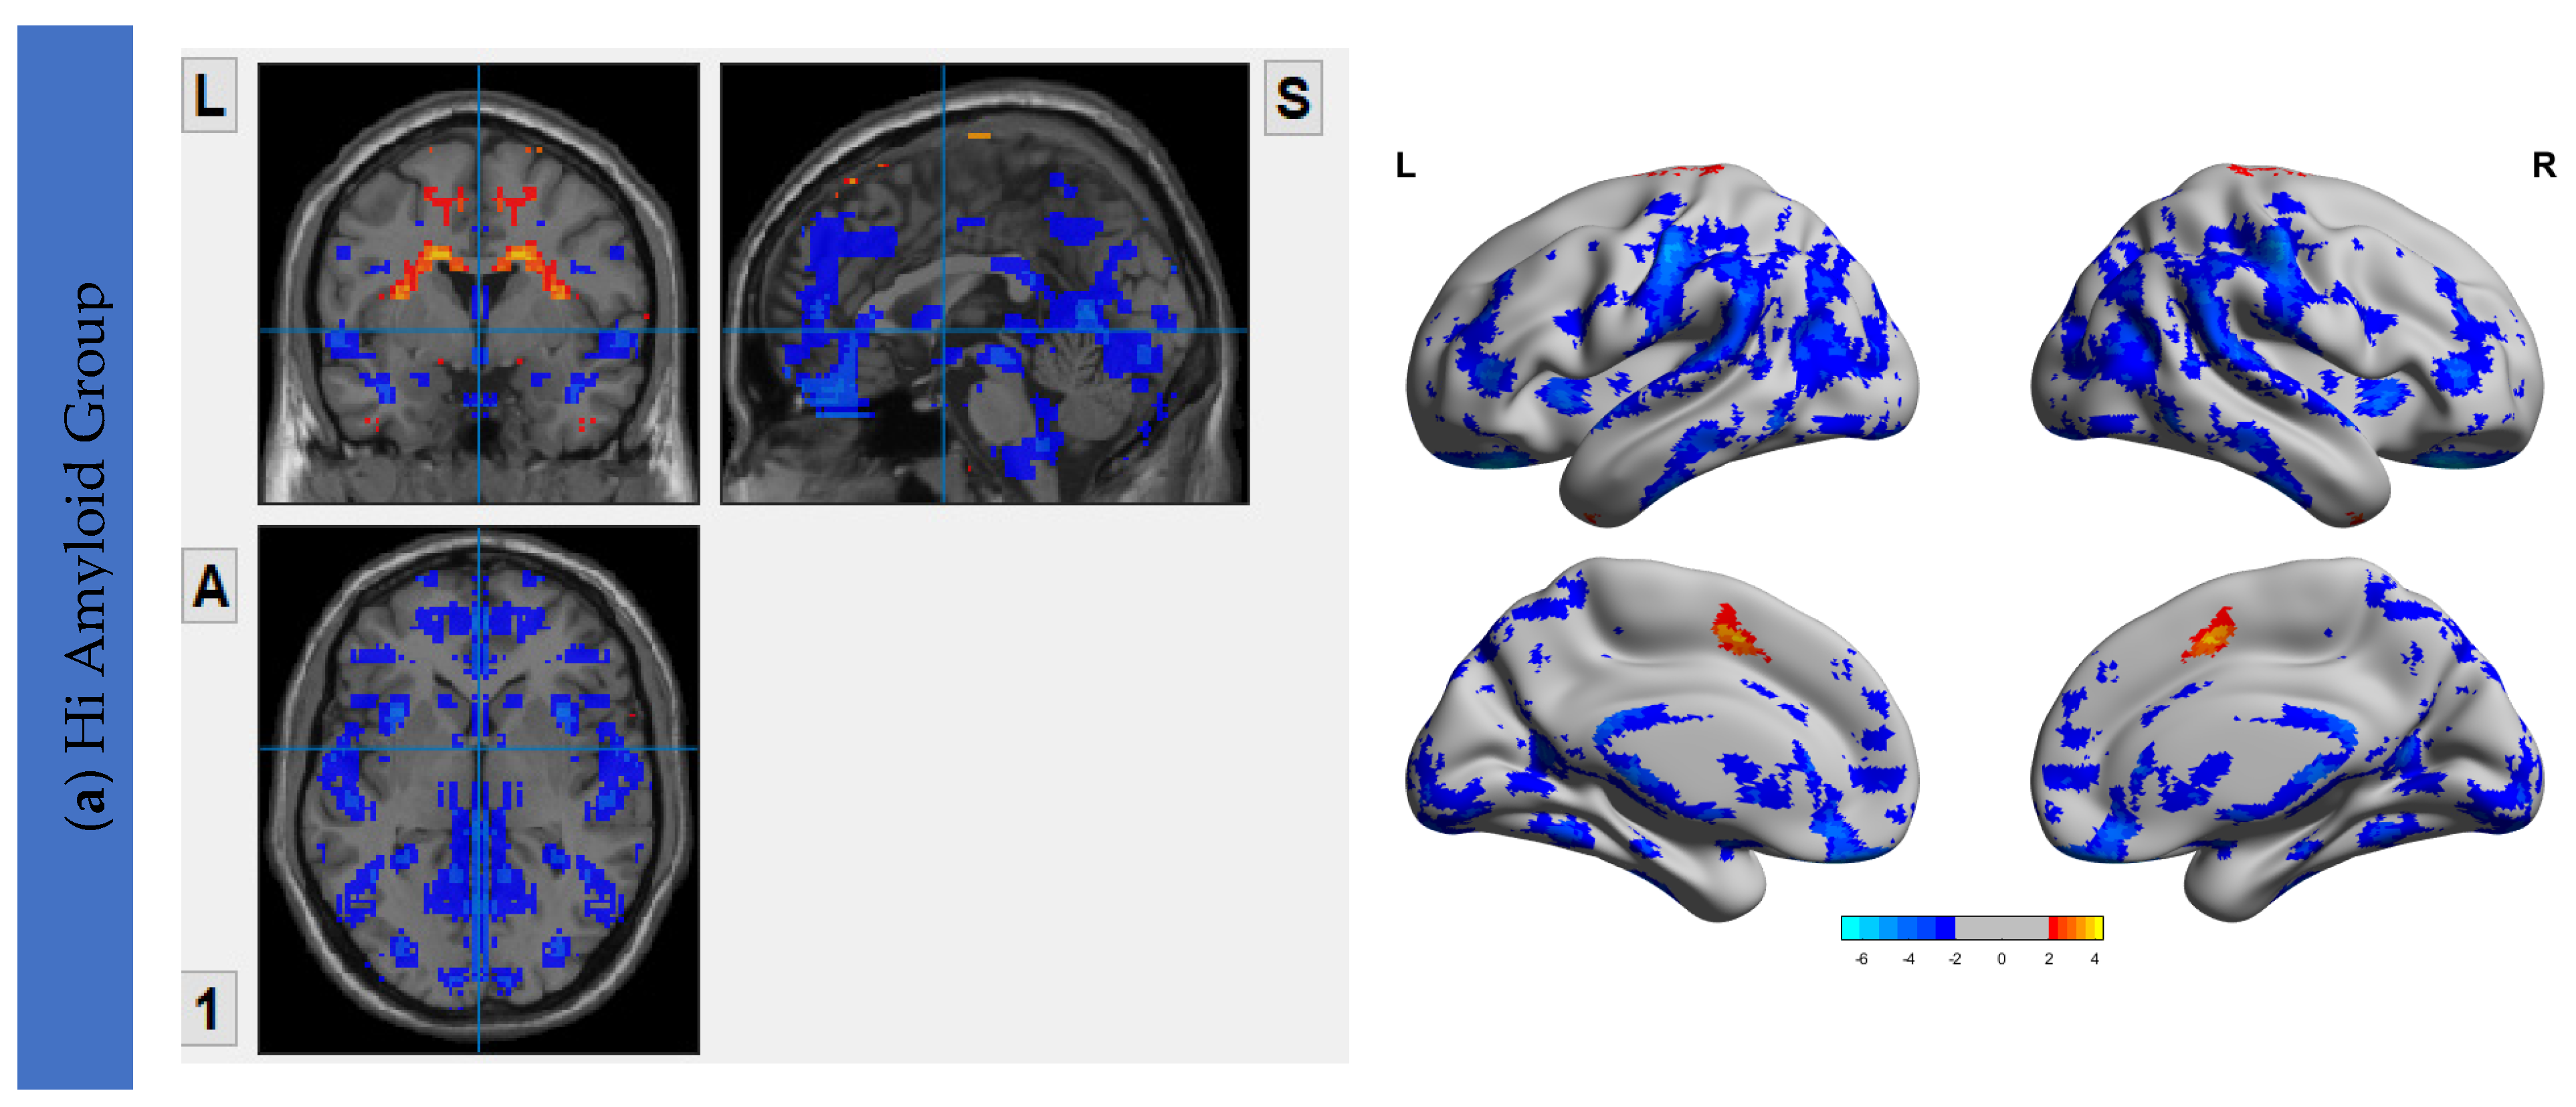

6.3. Interhemispheric Functional Connectivity (VMHC) Maps